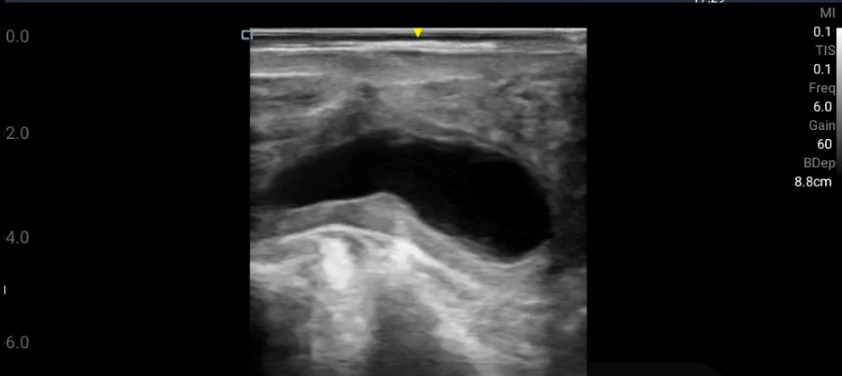

実際の子宮粘液症のエコー画像がこちらになります。

↑胎水・・?粘液・・・?

パッと見では妊娠なのか、子宮粘液症なのかの判断は難しいと思います。また厄介なポイントとして、「子宮粘液症を発症していると発情が来ないことが多い」ということも挙げられます。つまり一度妊娠と誤って判断されると、そのまま予定日までいってしまう可能性もあります。

もちろん胎子・胎盤の有無、胎膜スリップ、子宮角の左右差、子宮動脈などの状態から妊娠との判別は可能です。